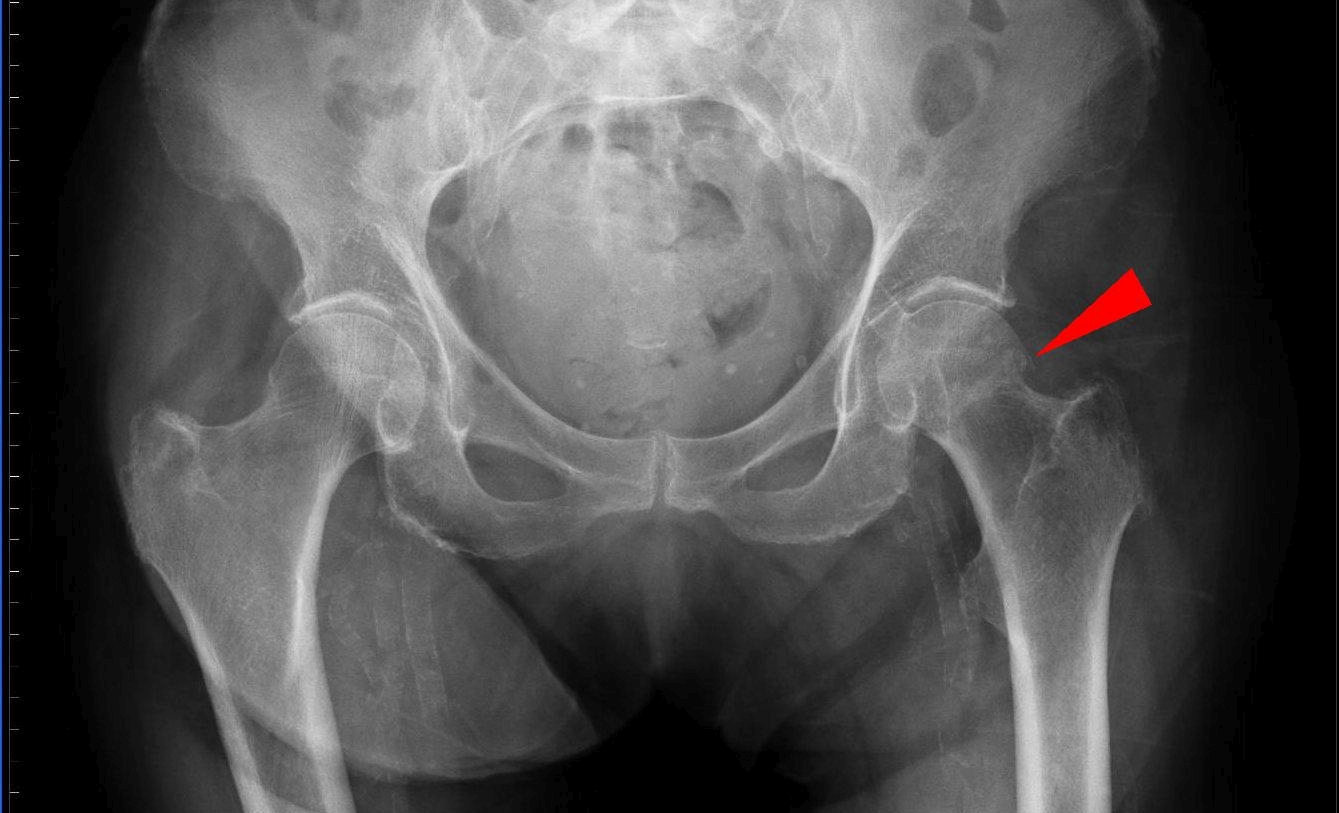

Η οστεοπόρωση είναι τόσο δύσκολο να διαγνωσθεί σε πρώιμο στάδιο ώστε αποκαλείται δικαίως «σιωπηλή νόσος». Πώς θα σας φαινόταν όμως αν η τεχνητή νοημοσύνη μπορούσε να βοηθήσει στην πρόγνωση της οστεοπόρωσης προτού καν επισκεφθείτε κάποιον ειδικό;